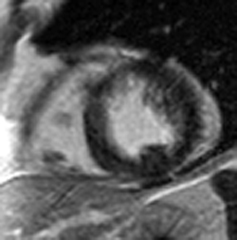

1) This gradient echo cine shows which of the following abnormalities?